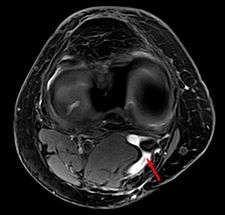

Baker's cyst on axial MRI with communicating channel between the semimebranosus muscle and the medial head of the gastrocnemius muscle.